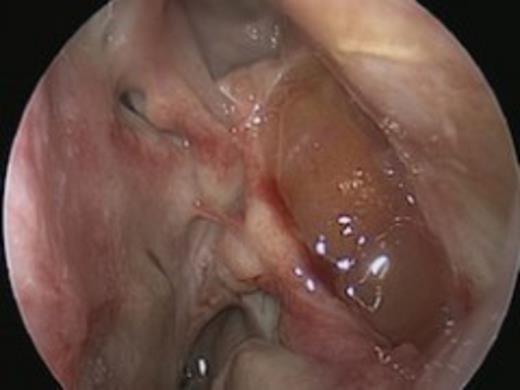

The radiological findings correlated with the clinical observations and the patient underwent Functional Endoscopic Sinus Surgery (FESS) to drain the large septic collection in the left maxillary antrum.

The operative findings included significant septic secretions within the left middle meatus and gelatinous soft tissue within the left maxillary antrum, which was sent for histological analysis. The infection was managed with appropriate antibiotics according to sensitivities, in addition to steroid nasules.

There was evidence of possible recurrence along the posterior and lateral wall of the maxillary sinus at routine follow-up. Hence, the patient underwent a revision left FESS and canine fossa puncture. Examination under anaesthesia was performed with 0, 45, and 70 degrees scopes respectively. This revealed recurrence in the posterior wall of the maxillary antrum, which was debrided to a shell of bone. Passage of the 70 degree scope through the canine fossa puncture demonstrated a further mass of abnormal mucosa which was completely debrided along the floor of the orbit. There were no postoperative complications, and follow-up was arranged for a month thereafter.